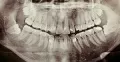

• По данному снимку, в первую очередь, следует удалить все зачатки зубов мудрости. Более правильным, с точки зрения окклюзионного взаимоотношения зубов, будет установить имплантаты после расширения зубного ряда. Чтобы точно составить план лечения, необходима дополнительная диагностика - телерентгенограмма, анализ гипсовых моделей челюстей и прикуса.